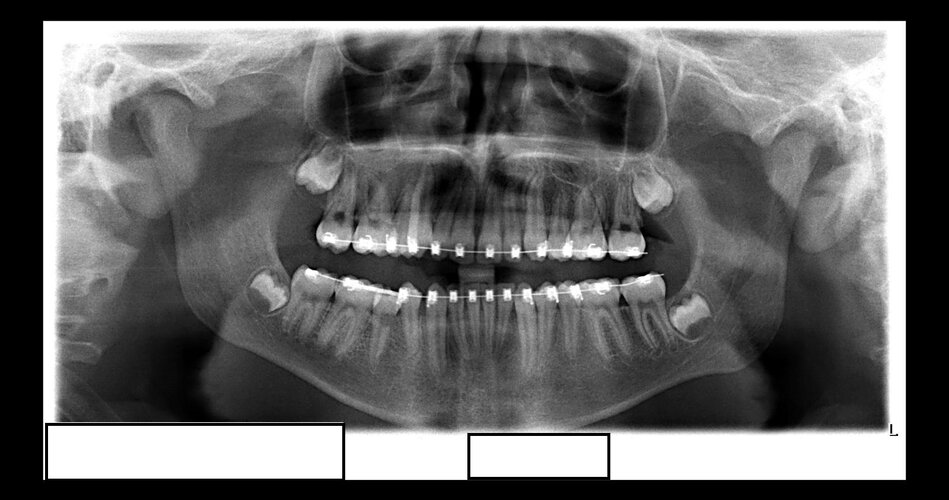

The Orthodontist took a picture of my mouth last week and told me it looked like i had external resorption he told me i should go to the dentist to get a more precise x-ray and so i did i just came back from that and they told me i do in fact have External Resorption and told me that i should contact a endodontist she listed two possible treatments she talked about cleaning up the root of the tooth and filling it up or if that wasnt possible according to the endodontist, we would have to extract what should i do and do these surgeries impact looks because im skeptical the orthodontist actually extracted and contracted my ass so i dont wanna be fucked again